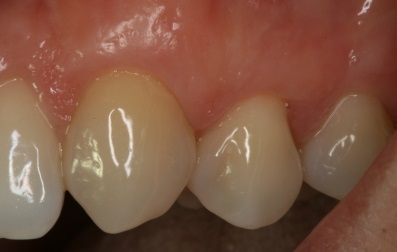

Υφίζηση ούλων σε δύο γειτονικά δόντια που οφείλεται σε τραυματικό βούρτσισμα. Πολύ έντονη ευαισθησία σε θερμικά ερεθίσματα

Κάλυψη της υφίζησης ούλων με ουλικό μόσχευμα